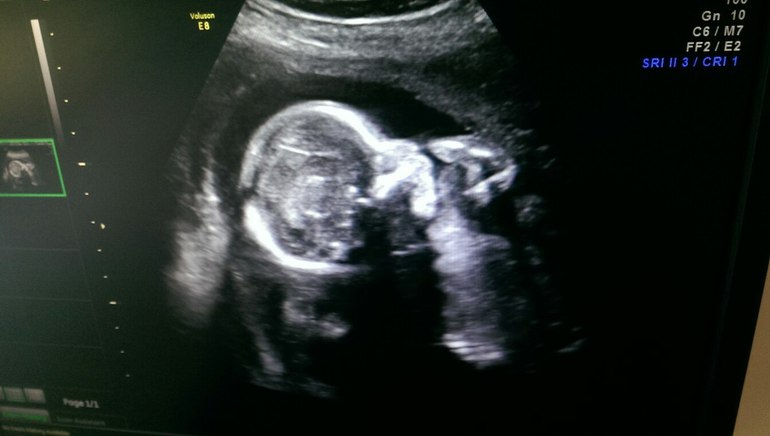

Результаты: УЗИ, КТГ, доплера, скринингаПлод ДЕВОЧКА, лежит поперек, головой влево» - это первое, что я услышала от врача, как только навели датчик...

Моя маленькая, хорошенькая, ручкой махала, в датчик пинала…

Все посмотрели, все посчитали, все в норме, отклонений нет...

По граммам доченька примерно 250 (БПЖ - ОЖ), совсем крошечка… Единственное нам не сказали КТР и сердечко не включили, какая ЧСБ тоже не написали(((

Очень переживала, когда лежала с пиелонефритом, кололи антибиотики 5 дней, но все обошлось, узист сказал, что девочка развивается в срок, здоровая, придраться не к чему!